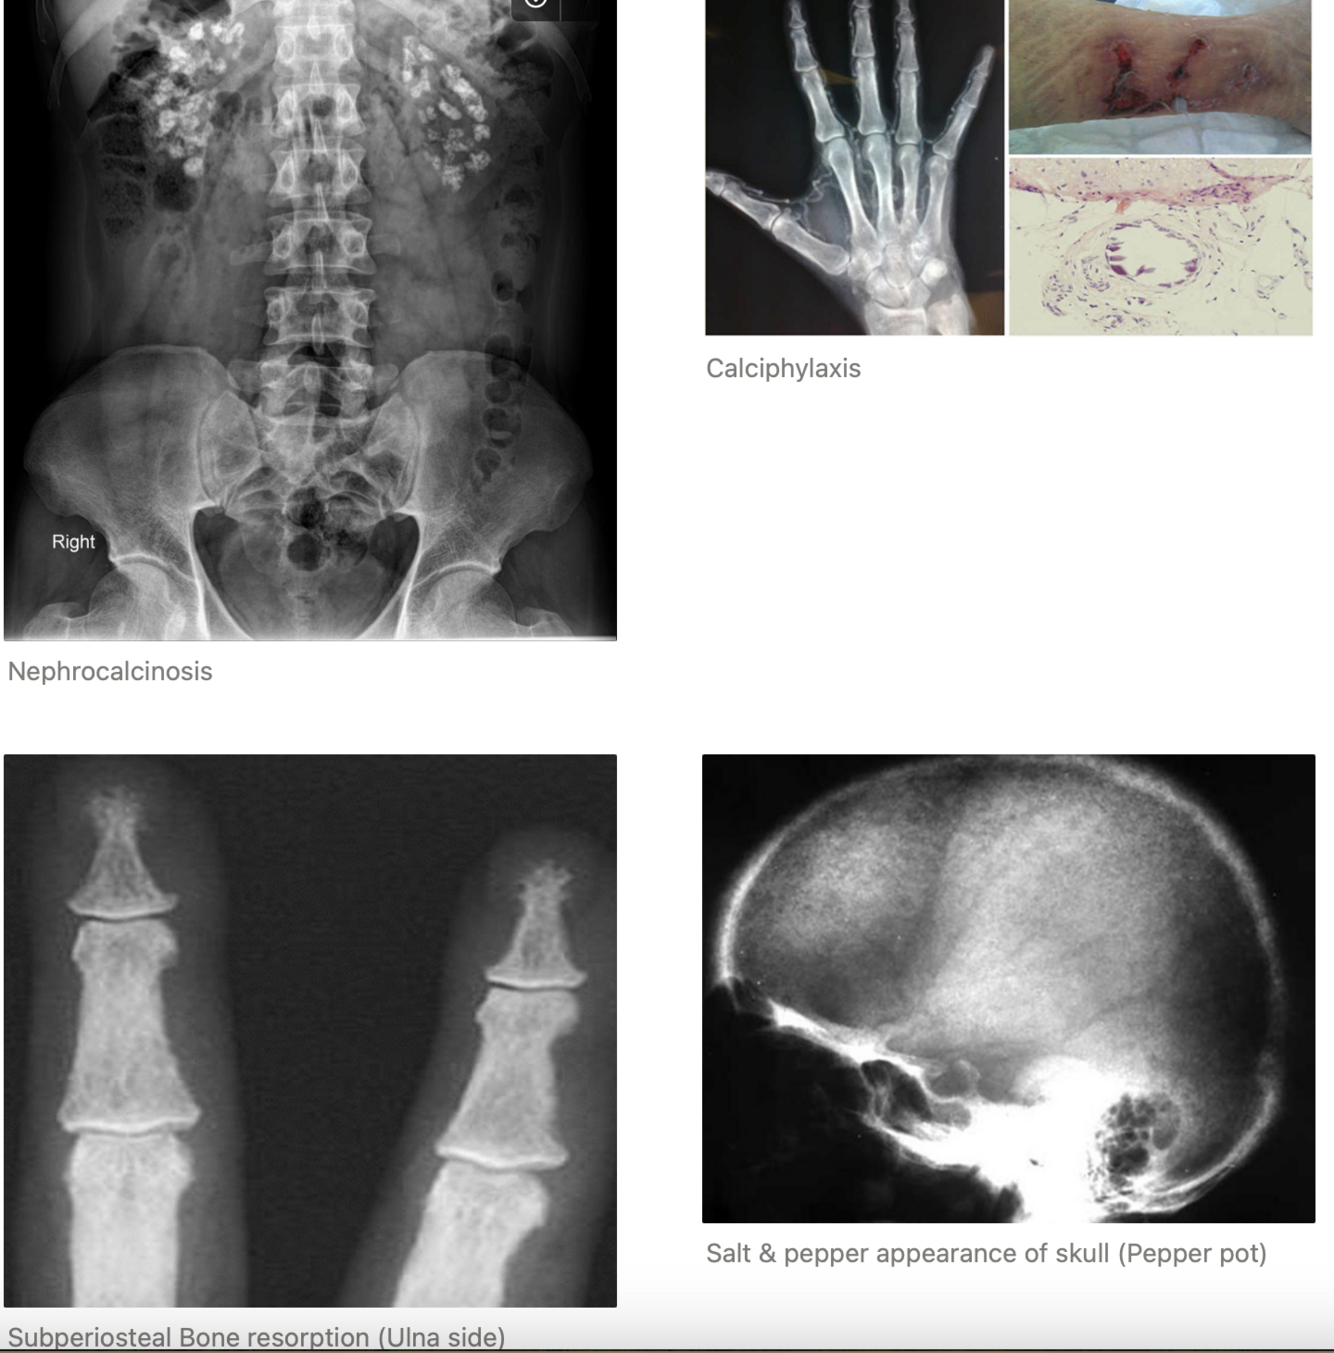

• STONE: Renal calculi (15-20%), Nephrocalcinosis (calcium oxalate and calcium phosphate deposition in renal parenchyma - 10.2%).

• CVS: HPT, Valvular calcification, Calciphylaxis (Ca2+ deposit in small vessels → blood clots, painful skin ulcers, infection), left ventricular hypertrophy, aortic valve calcification, increased aortic stiffness and increased intimal media thickness. Reduced QT interval ( Tacycardic)

X-ray - Hands, Clavicle & Skull: look for resorption signs & cystic formation, punched out skull lesion. Pelvis to screen for silent nephrolithiasis or nephrocalcinosis.